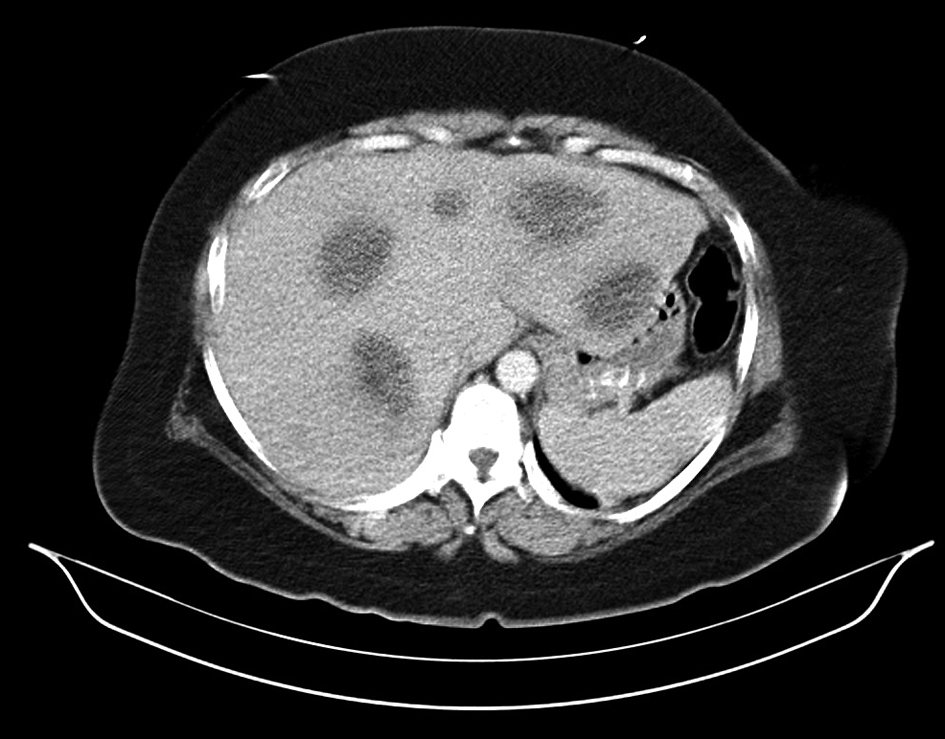

Hypercalcemia as a Presenting Clinical Manifestation of Adenocarcinoma of the Colon

Figures